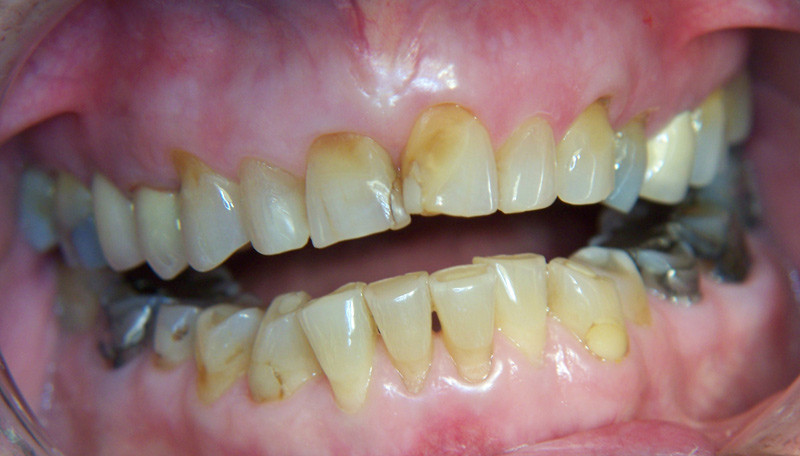

Osteonekrose i kjevene hos pasienter som bruker bisfosfonater ble første gang beskrevet i 2003 (4, 5). Det synes å være en klar sammenheng mellom langvarig bruk av bisfosfonater og kjeveosteonekrose, særlig hos kreftpasienter som har fått bisfosfonater ved infusjon. Bevisene for en slik sammenheng vanskeliggjøres ved at disse pasientene vanligvis har en annen komorbiditet og tar en rekke andre medikamenter som analgetika, steroider og cytostatika. Men det er også rapportert om mange tilfeller med kjeveosteonekrose hos osteoporosepasienter som kun har stått på perorale bisfosfonater (6). Vi har ikke funnet litteratur som omhandler kjeveleddsdestruksjon og langvarig bruk av bisfosfonater. Ettersom bisfosfonatene griper inn i beinets utskiftningsmekanismer bl.a. ved å hemme osteoklastfunksjonen og angioneogenesen (7) er en slik sammenheng ikke usannsynlig.

Behandling av bittproblemene hos vår pasient synes å være en stor utfordring, idet bittåpningen er for stor til å la seg korrigere ved bittsliping og protetisk kroneterapi. Ettersom dette synes å være en pågående destruksjonsprosess, er dessuten residiv overveiende sannsynlig etter en slik behandling. Den mest aktuelle behandlingen ville trolig være kirurgisk rekonstruksjon av kjeveleddene med ribbeintransplantat, ev. innsettelse av totalproteser i kjeveledd.

Degenerative kjeveleddslidelser med bittforandringer som beskrevet hos vår pasient, er meget sjeldne hos ellers friske pasienter. Pasienten har ikke vært utsatt for skade eller fått medisinering som kunne tenkes å ha patogenetisk betydning, f.eks. kortikosteroider, annen hormonbehandling, strålebehandling eller cytostatika. Vi anser derfor den langvarige medikasjonen med bisfosfonater som en svært sannsynlig årsak til kjeve- og femurproblemene.